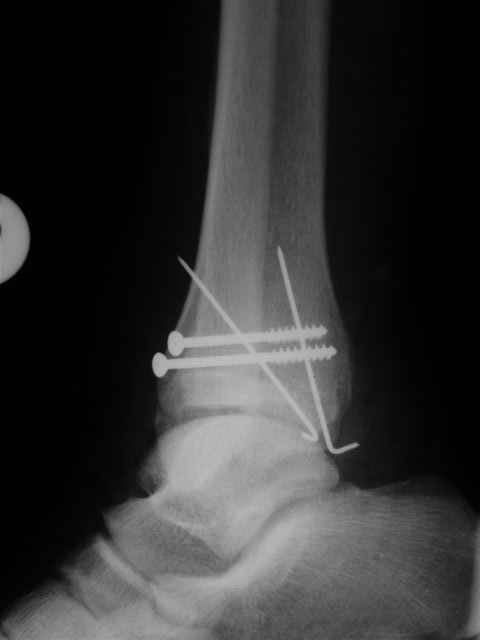

В первом письме я упомянул о закрытом повреждении правого голеностопного сустава, эверсионно-пронационный механизм травмы - перелом внутренней лодыжки( поперечный, на уровне суставной щели) и отрывной перелом бугорка Chaput. После обработки открытых переломов бедра и большеберцовой кости в эту же сессию перелом внутренней лодыжки фиксировал двумя расходящимися спицами, бугорок Chaput двумя тягловыми винтами 3,5 мм. Раны заживают благополучно. Учитывая повреждение наружной группы мышц, активное разгибание в голеностопном суставе ограничено. Пассивная + пассивно-активная мобилизация голеностопного сустава с физиотерапевтом.